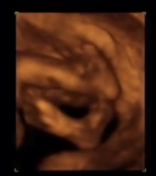

Desarrollo del feto en la semana 26: Empieza a engordar

En esta semana de desarrollo fetal tu bebé pesará casi un kilo y medirá alrededor de 35,5 centímetros desde la coronilla de su cabeza hasta los pies.